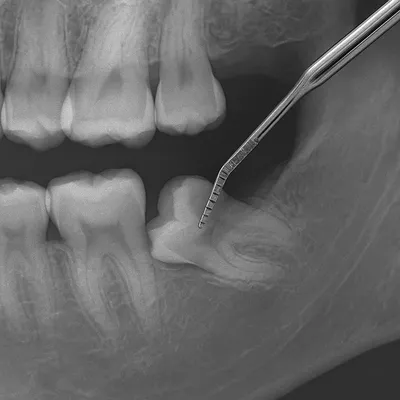

رادیوگرافی دقیق مولر سوم نهفته با پروب دندانپزشکی

شناخت اینکه دندان عقل شماره چند است فقط یک موضوع آموزشی ساده نیست، بلکه در روند درمانی و تشخیصی نقش مستقیم دارد. وقتی شماره دقیق دندان عقل مشخص باشد، ثبت اطلاعات در پرونده دندانپزشکی دقیقتر انجام میشود و احتمال اشتباه در درمان کاهش مییابد.

این موضوع بهویژه در جراحی دندان عقل، کشیدن دندان نهفته یا بررسی التهاب لثه اهمیت زیادی دارد. علاوه بر این، در زمان مشاهده تصاویر رادیوگرافی مانند OPG و CBCT، دانستن شماره هر دندان کمک میکند هم بیمار و هم دندانپزشک متوجه شوند مشکل دقیقاً مربوط به کدام ناحیه است.

وقتی بیمار بداند دندان عقل شماره چند است، بهتر میتواند در گزارشهای پزشکی و تصاویر رادیوگرافی مثل OPG یا CBCT جایگاه دقیق این دندان را تشخیص دهد.

چرا دندان عقل را در گزارش رادیوگرافی با شماره مینویسند؟

وقتی روی عکس OPG یا CBCT بررسی انجام میشود، دندانپزشک باید دقیقاً مشخص کند مشکل مربوط به کدام دندان است. استفاده از شمارهگذاری، ابهام را برطرف میکند و از اشتباه در تشخیص یا جراحی جلوگیری میشود.